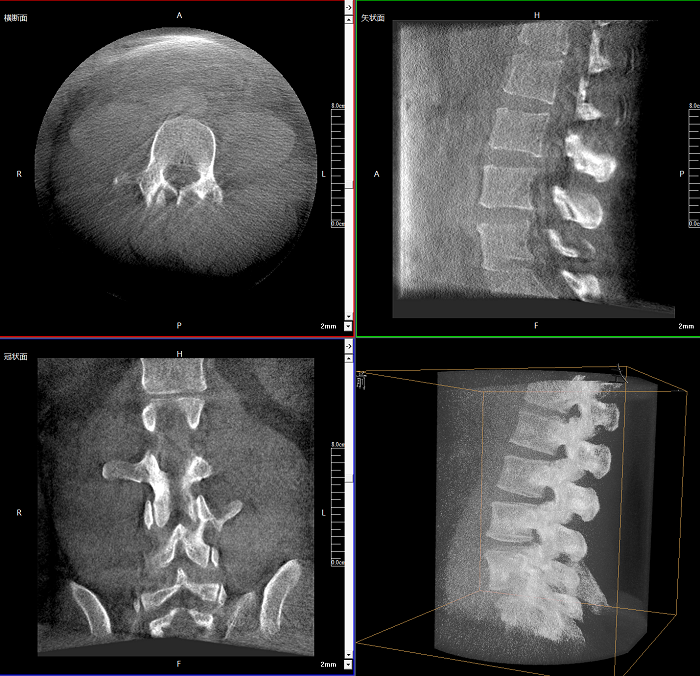

三維成像 全面觀察

任意視角、任意切面觀察

術中實時生成橫斷面、矢狀面、冠狀面及三維影像,可在任意切面、任意角度評估植入物和解剖結構的相對位置。

100%視野范圍提升

較9英寸常規(guī)平板視野提升100%,幫助醫(yī)生迅速判斷椎體節(jié)段,定位手術部位。

400萬像素成像

易于觀察細微病灶,利于胸部、腹部、脊柱關節(jié)等復雜骨骼和軟組織的成像。

Clinical picture

臨床圖片